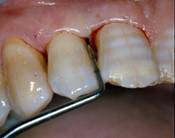

Fig 12

Clinical re-evaluation 9 months after surgery

Int J Med Sci Image

At 9 months from the procedure the dental elements were virtually stables, with a mean gCAL (gain hi clinical attachment) of 2.6mm; radiographic evaluation showed defect filling and good prognosis [fig. 12-13].